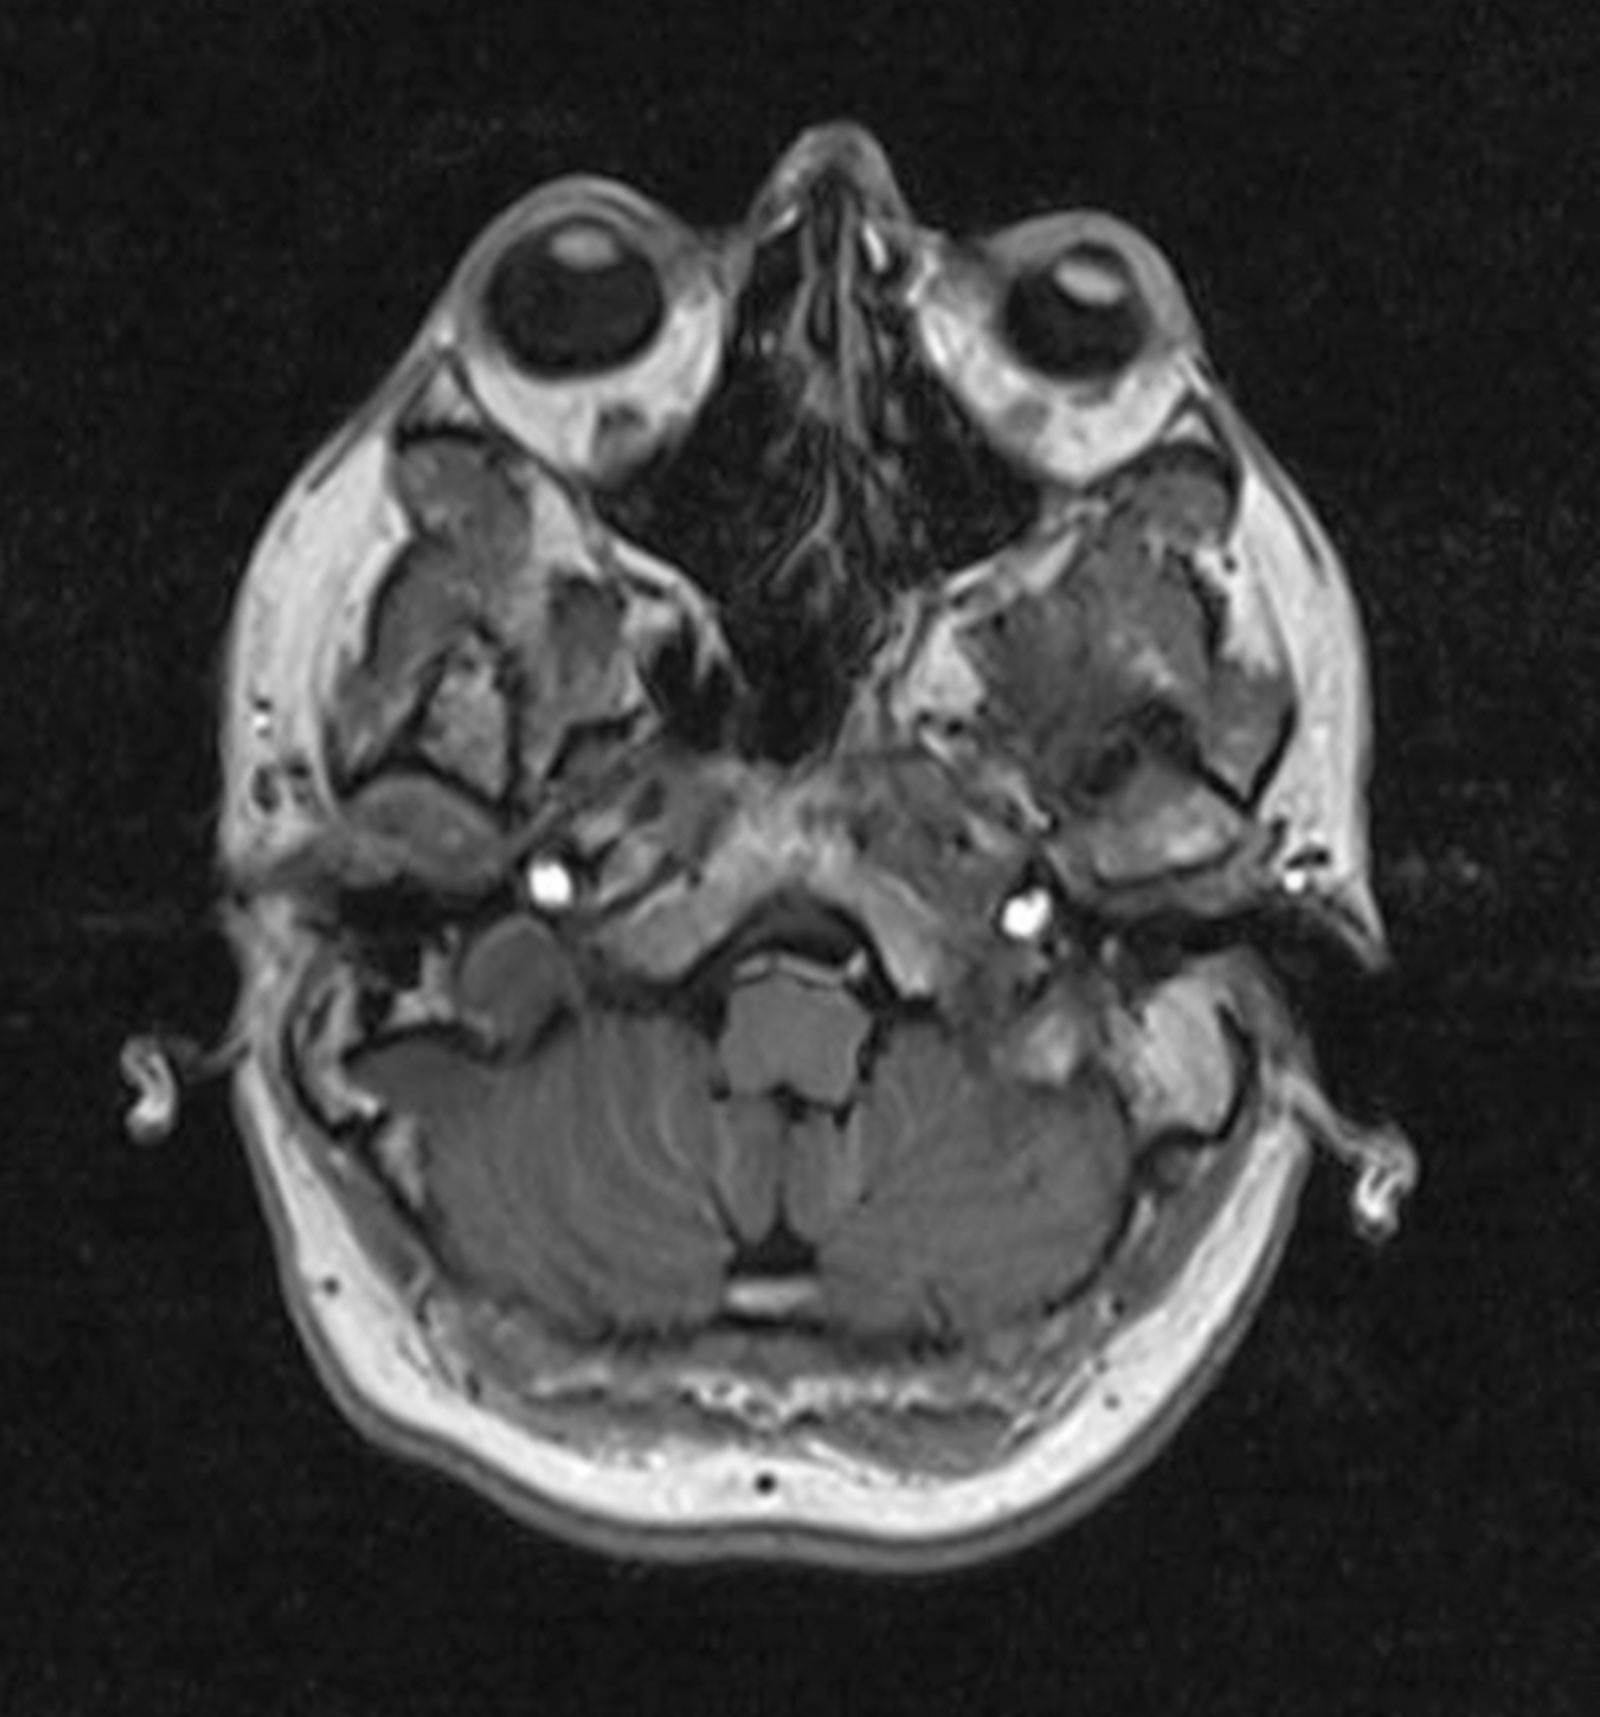

My own interpretation of my MRI brain - normal crystalline lenses.

When I finally received the written report, it felt like finals exam results day. Pass or fail, my future depended on it. I ripped open the envelope and quickly scanned the document. My eyes alighted on the words “… una normal configuración de la corteza cerebral…” Even without Google translate, I breathed a sigh of relief. However, there was the customary sting in the tail that I have come to expect. As I read further through the report it continued “…aislados focos hiperintensos en la sustancia blanca hemisférica, en probable relación con microangiopática isquémica crónica, no patológico para la edad.” Essentially isolated ischaemic white matter changes related to ageing and a brief nod to my own mortality. “Dammit!” as Jack Bauer would say [1].